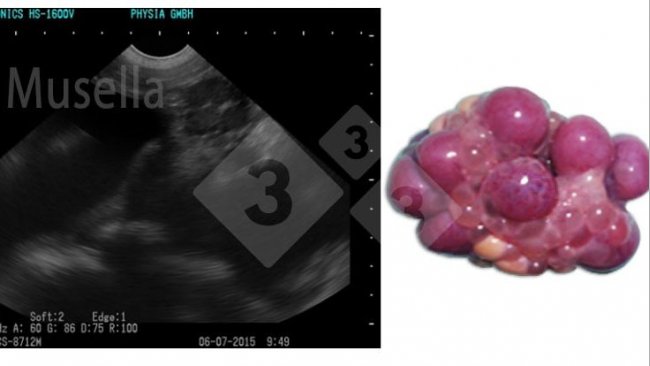

Ecografia de precisão em porcas: muito mais que controlo de gestação!

A ecografia pode ser usada para visualizar as estruturas ováricas, avaliar o estado puberal e diagnosticar patologias ováricas.